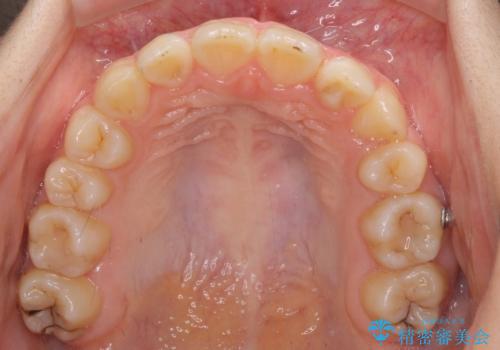

- 目立つ八重歯を改善したいとのことで来院された患者様です。

奥歯の咬み合わせは左右とも理想的なものでしたが、下顎前歯が1本欠損しているため、上下のバランスを保つことが難しい歯列でした。

唇を閉じたときに上顎前歯が下顎の唇に乗っかる印象があったため、八重歯の後方にある小臼歯を1本抜歯することとしました。

変則的な抜歯となるため、臼歯の咬合が理想的でなくなることが懸念されますが、インビザラインにて矯正治療を行うこととしました。

まずは補助装置を用いて八重歯を改善し、インビザラインにて歯列を整えましたが、当初の懸念が的中し、臼歯部の咬合を安定させることができませんでした。